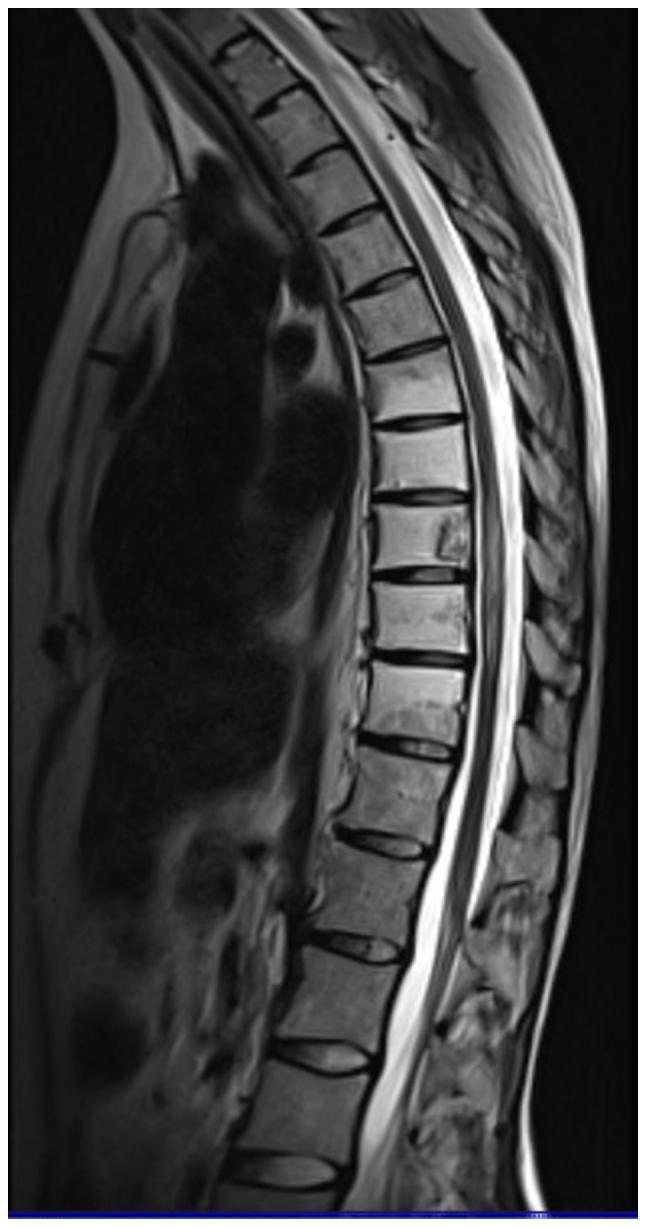

Immune checkpoint inhibitors (ICIs) have revolutionized oncology, shifting the approach from directly targeting tumor cells to enhancing the immune response of the host towards tumor cells by blocking inhibitory receptors or ligands. The present report describes the case of a 26-year-old female patient diagnosed with a rare subtype of renal cell carcinoma (RCC), transcription factor E3-rearranged (t)RCC, who presented with progressing motor weakness of the lower extremities, along with urinary and fecal incontinence, which had begun 3 days prior to admission. A diagnosis of longitudinally extensive transverse myelitis (LETM) was made, resulting in the administration of methylprednisolone and intravenous immunoglobulin. Subsequently, the condition of the patient markedly improved. LETM, a rare and potentially life-threatening condition, manifests through symptoms such as pain, sensory deficits, motor impairments and disturbances in bladder and rectal function. The positive neurological outcome in the patient in the present case underscores the significance of timely intervention. Whilst the synergistic impact of combining radiotherapy and immunotherapy in cancer treatment is widely emphasized, their influence on the spectrum and severity of toxicities remains underexplored. The present case, documenting LETM after treatment of tRCC with pembrolizumab, sheds light on a rare neurological adverse effect of ICIs. It underlines the need for prompt action in the effective management of immune-related adverse effects. Furthermore, the present case serves as a noteworthy contribution to the evolving understanding of the intricate dynamics between immune modulation and treatment-related complications in the context of innovative cancer therapies.

免疫检查点抑制剂(ICIs)彻底改变了肿瘤学,将治疗方法从直接靶向肿瘤细胞转变为通过阻断抑制性受体或配体来增强宿主对肿瘤细胞的免疫反应。本报告描述了一名26岁女性患者的病例,该患者被诊断患有肾细胞癌(RCC)的一种罕见亚型,即转录因子E3重排(t)RCC,入院前3天开始出现下肢进行性运动无力,伴有大小便失禁。诊断为纵向广泛横贯性脊髓炎(LETM),随后给予甲泼尼龙和静脉注射免疫球蛋白治疗。患者病情随后明显改善。LETM是一种罕见且可能危及生命的疾病,其症状包括疼痛、感觉障碍、运动障碍以及膀胱和直肠功能紊乱。本病例患者积极的神经学转归凸显了及时干预的重要性。虽然放疗和免疫疗法联合在癌症治疗中的协同作用被广泛强调,但其对毒性谱和严重程度的影响仍未得到充分探索。本病例记录了帕博利珠单抗治疗tRCC后出现LETM的情况,揭示了ICIs一种罕见的神经学不良反应。它强调了在有效管理免疫相关不良反应方面迅速采取行动的必要性。此外,本病例为在创新癌症治疗背景下不断发展的对免疫调节与治疗相关并发症之间复杂动态关系的理解做出了值得注意的贡献。